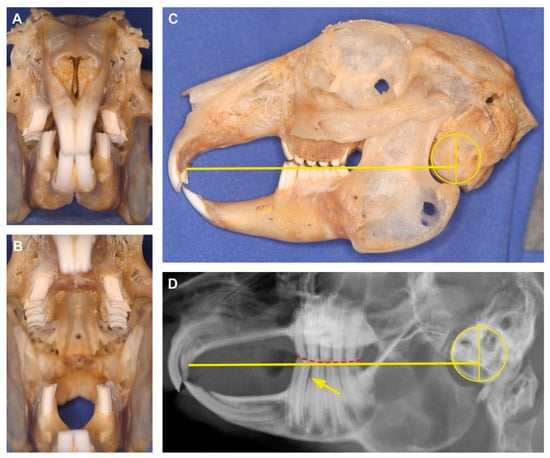

| Skull base plane | Line connecting the rostral end of the hard palate immediately caudal to the second incisor and the ventral border of the tympanic bullae |

| Facial tilt angle | Angle between the palatal plane and the occipital plane |

| Nasal angle | Angle between the nasal plane and the skull base plane |

| Occipital angle | Angle between the occipital plane and the skull base plane |

| Palatal angle | Angle between the palatal plane and the skull base plane |